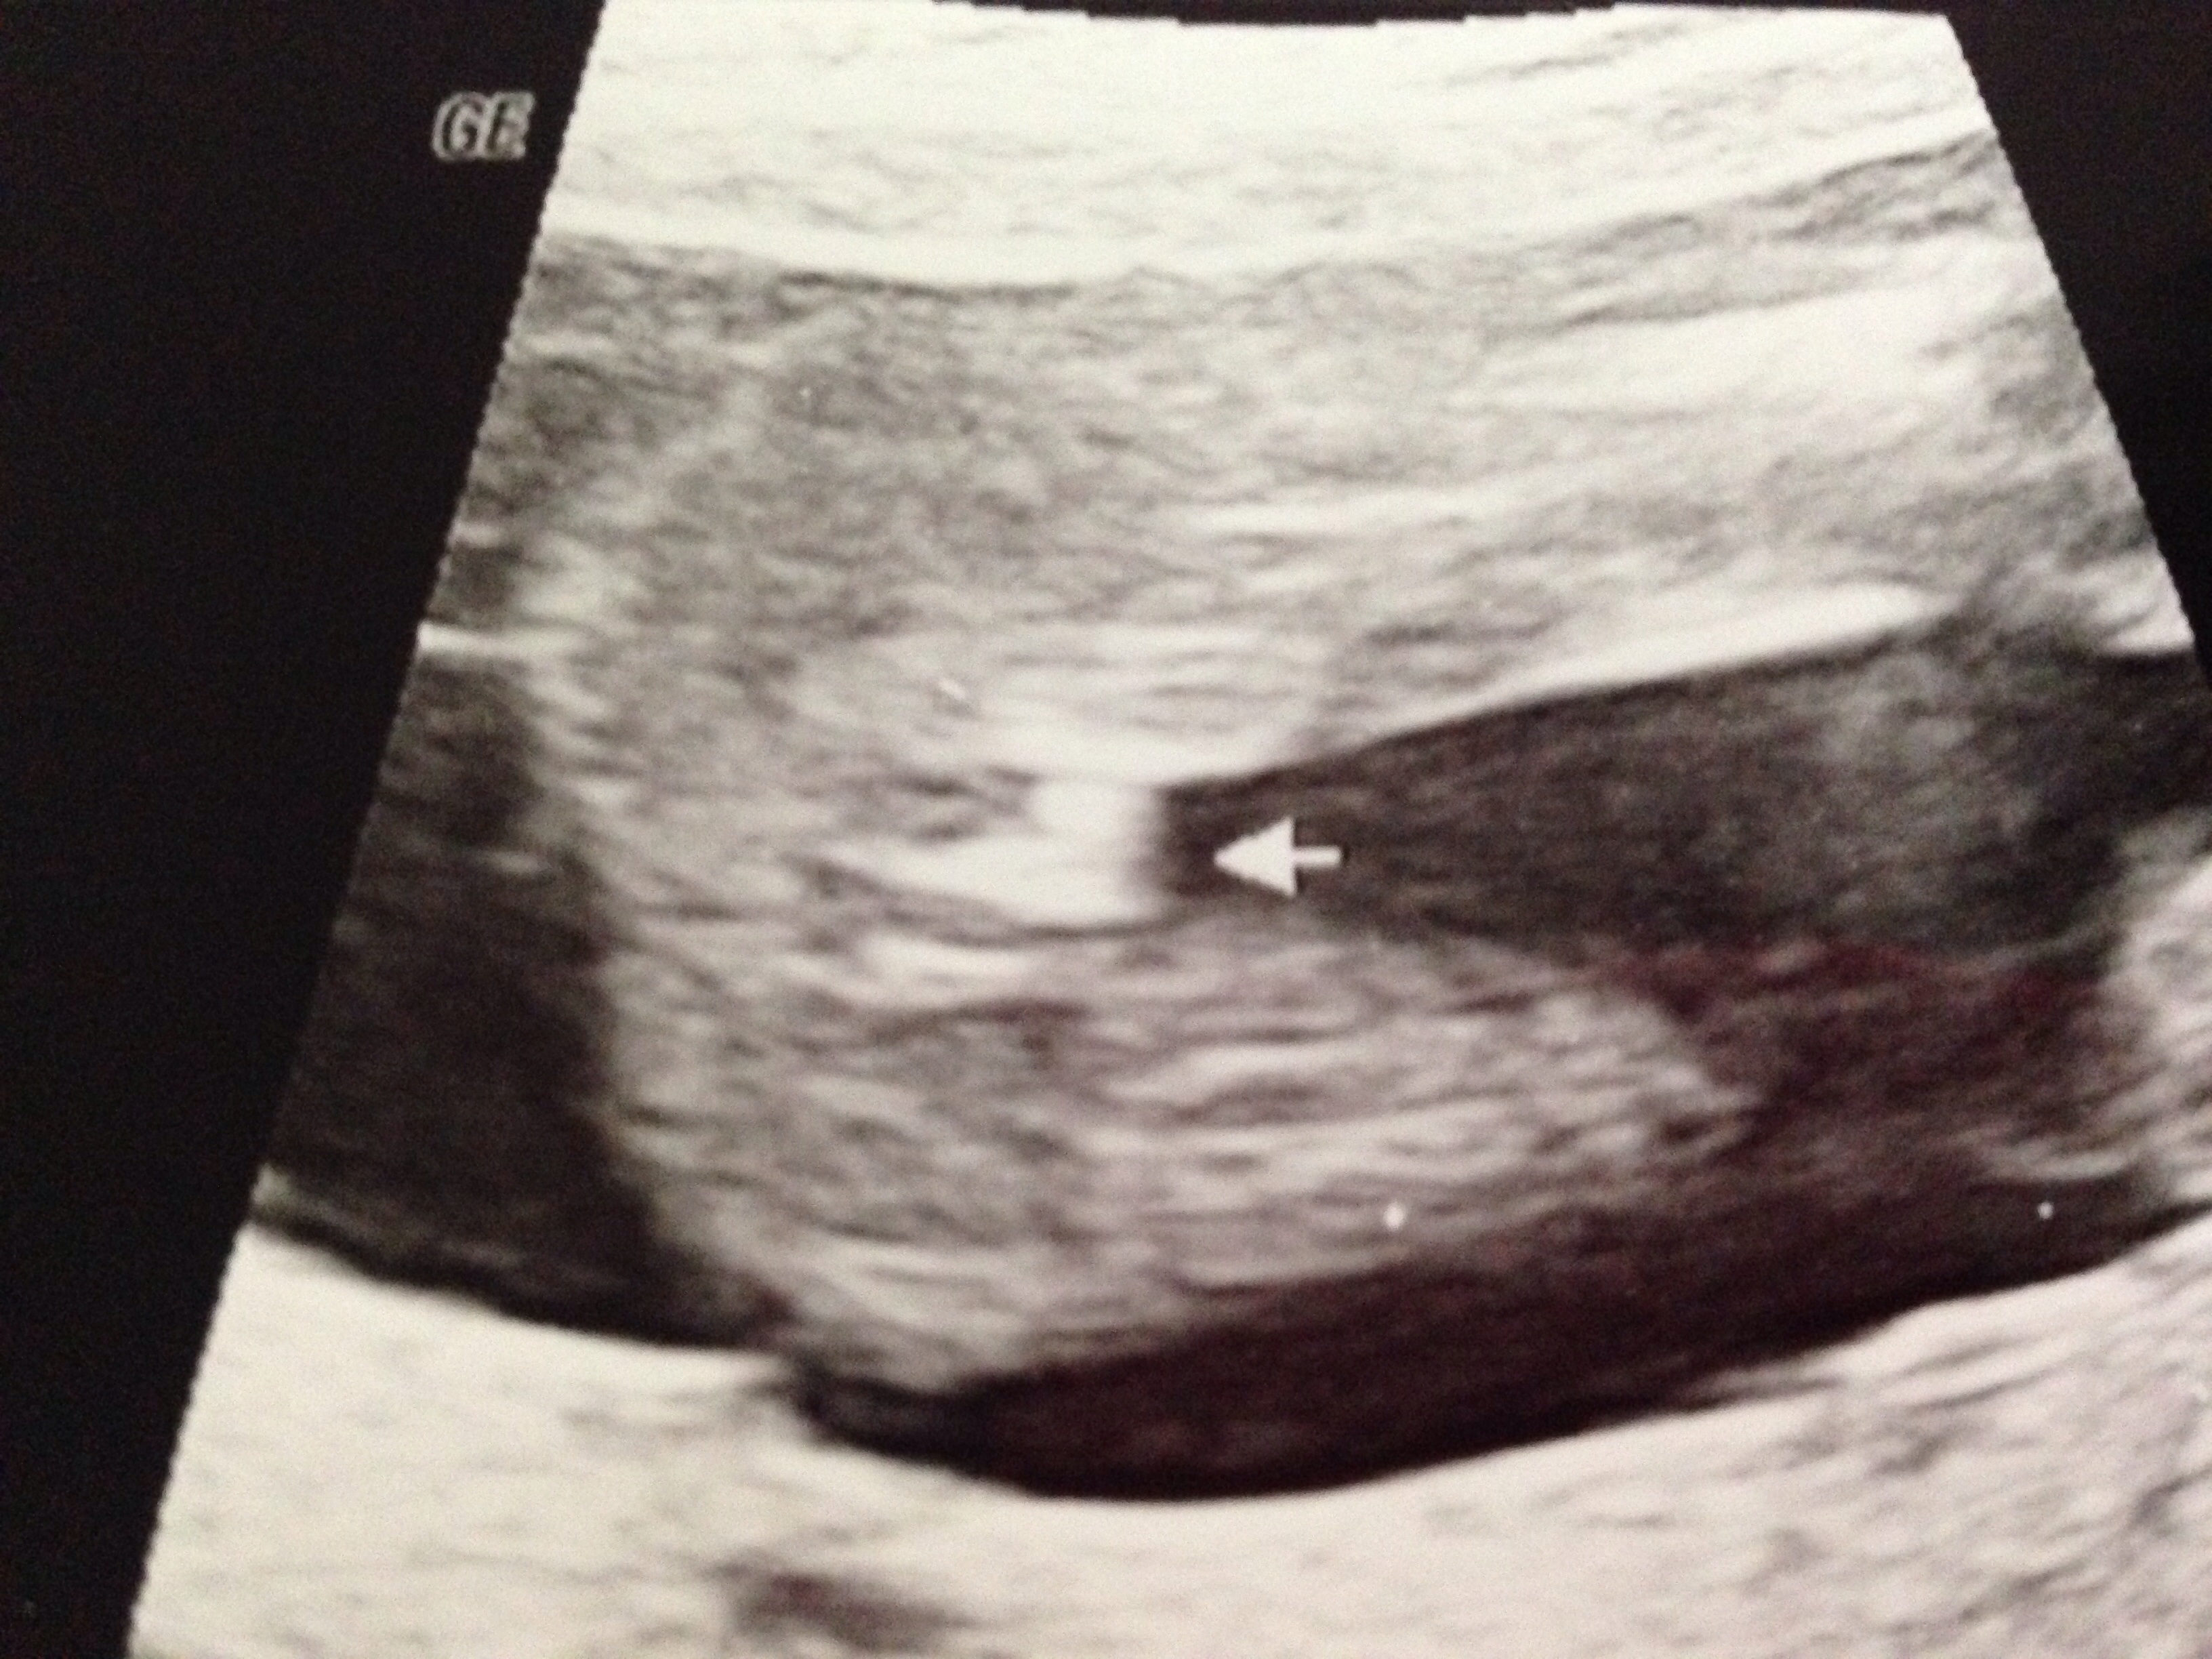

Sweet DH took me to get a gender US for my birthday. I am 16w2d. The tech said she was 85% sure...but kept saying yes, she was right. But, she wants us to come back next week for a free recheck. So...what do y'all think?? I don't see a 'turtle'...but no definite 'lines' either...